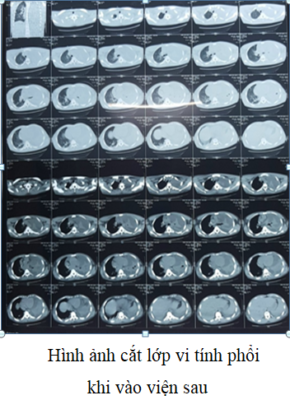

Bệnh nhân nam, 19 tuổi, tiền sử khỏe mạnh. Cách nhập viện 8 ngày biểu hiện mệt mỏi, ho, sốt, đau tức ngực trái. Nhập viện vào khoa Hồi sức cấp cứu, Bệnh viện Quân y 17 trong tình trạng rất nặng với triệu chứng mệt nhiều, sốt cao, khó thở, suy hô hấp. Khoa Hồi sức cấp cứu đã tiến hành cấp cứu kịp thời, thực hiện đặt nội khí quản, thở máy, nội soi khí phế quản để tầm soát tổn thương, lấy mẫu bệnh phẩm cấy khuẩn và làm kháng sinh đồ. Kết quả xét nghiệm máu cho thấy tình trạng nhiễm trùng máu rất nặng. Kháng sinh phổ rộng được sử dụng ngay lập tức theo kinh nghiệm. Kết quả chụp cắt lớp vi tính phổi trái bị xẹp hoàn toàn, có nhiều đám tổn thương đông đặc và tràn dịch màng phổi mức độ nhiều. Ngay khi có kết quả cấy đờm là vi khuẩn Burkholderia pseudomallei và kháng sinh đồ nhạy cảm với một số kháng sinh. Bệnh nhân được điều trị ngay theo kháng sinh đồ và đáp ứng tốt với kháng sinh. Bệnh diễn biến khá hơn, hết sốt, tuy nhiên vẫn còn đau ngực trái nhiều, khó thở. Chụp lại cắt lớp vi tính lồng ngực phổi trái vẫn còn tổn thương nặng. Bệnh viện Quân y 17 đã hội chẩn với Bệnh viện 175, Bệnh viện Đà Nẵng thống nhất phẫu thuật mở ngực bóc vỏ phổi, làm sạch màng phổi, cắt lọc tổ chức phổi hoại tử, dẫn lưu khoang màng phổi, tiếp tục điều trị phối hợp thuốc, đồng thời tăng cường nuôi dưỡng tích cực, cân bằng nước điện giải, khoáng chất, tập phục hồi chức năng hô hấp. Sau 1 tháng điều trị, bệnh nhân phục hồi, toàn trạng ổn định, chuyển khoa khác tiếp tục điều trị duy trì